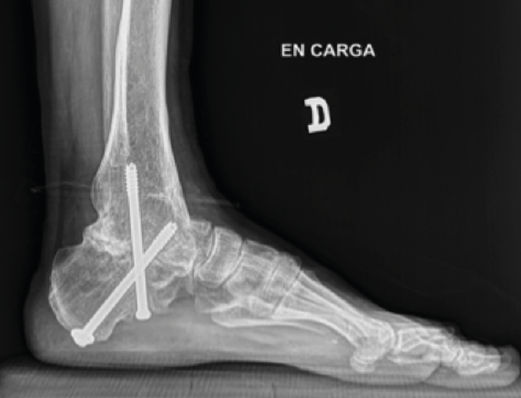

Figura 5. Control por radioscopia del aloinjerto.

- Tallado del injerto de manera intraoperatoria (Figuras 4 y 5).

Figura 9. Pseudoartrosis subastragalina.